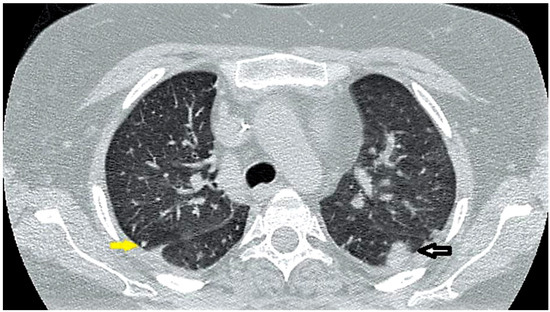

Hemophagocytic Lymphohistiocytosis (HLH): Elusive Diagnosis of Disseminated Mycobacterium avium Complex Infection

by Eloy E. Ordaya, Sulieman Abu Jarir, Robert Yoo and Pranatharthi H. Chandrasekar

Introduction: Hemophagocytic lymphohistiocytosis (HLH) is a clinical syndrome of hyperinflammation leading to an uncontrolled and ineffective immune response, associated with high mortality. Case report: A 26-year-old woman with acute lymphoblastic leukemia, 8 months in remission, was found to have HLH. Without any improvement, [...] Read more.

Introduction: Hemophagocytic lymphohistiocytosis (HLH) is a clinical syndrome of hyperinflammation leading to an uncontrolled and ineffective immune response, associated with high mortality. Case report: A 26-year-old woman with acute lymphoblastic leukemia, 8 months in remission, was found to have HLH. Without any improvement, stem cell transplantation was considered. Then, Mycobacterium avium complex (MAC) infection was identified as cause of her HLH. With appropriate therapy for infection, HLH improved and transplantation was averted. Conclusion: MAC should be included in the list of potential causes of HLH. Full article